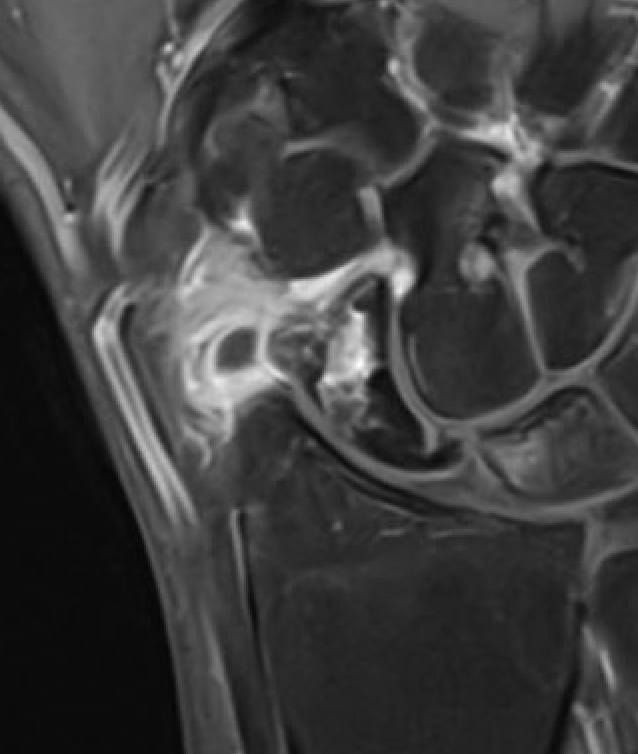

MRI

Low vascularity of scaphoid on T1 MRI and reduced gadolinium uptake proximal pole scaphoid